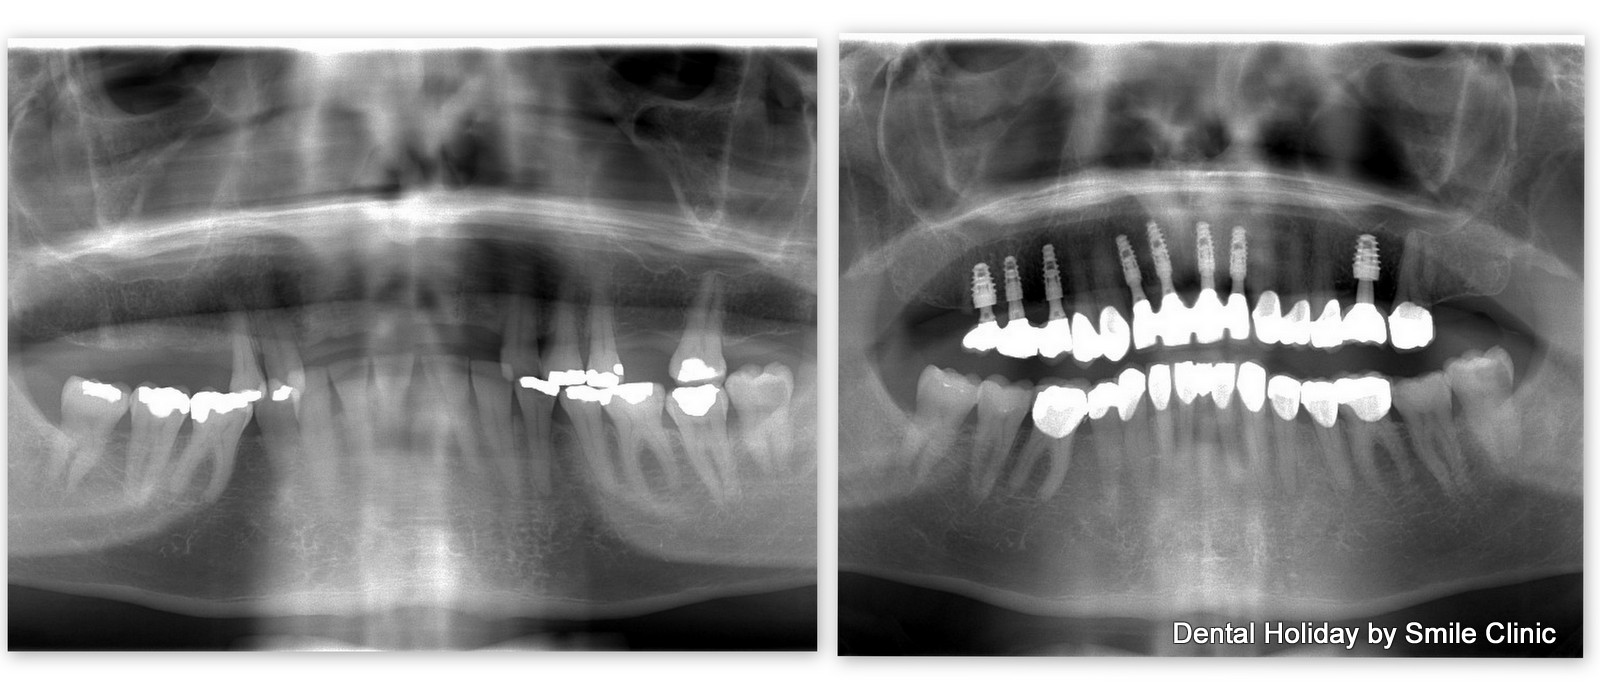

As you can see from the x-ray, Brian had just a handful of loose teeth left in his upper jaw.